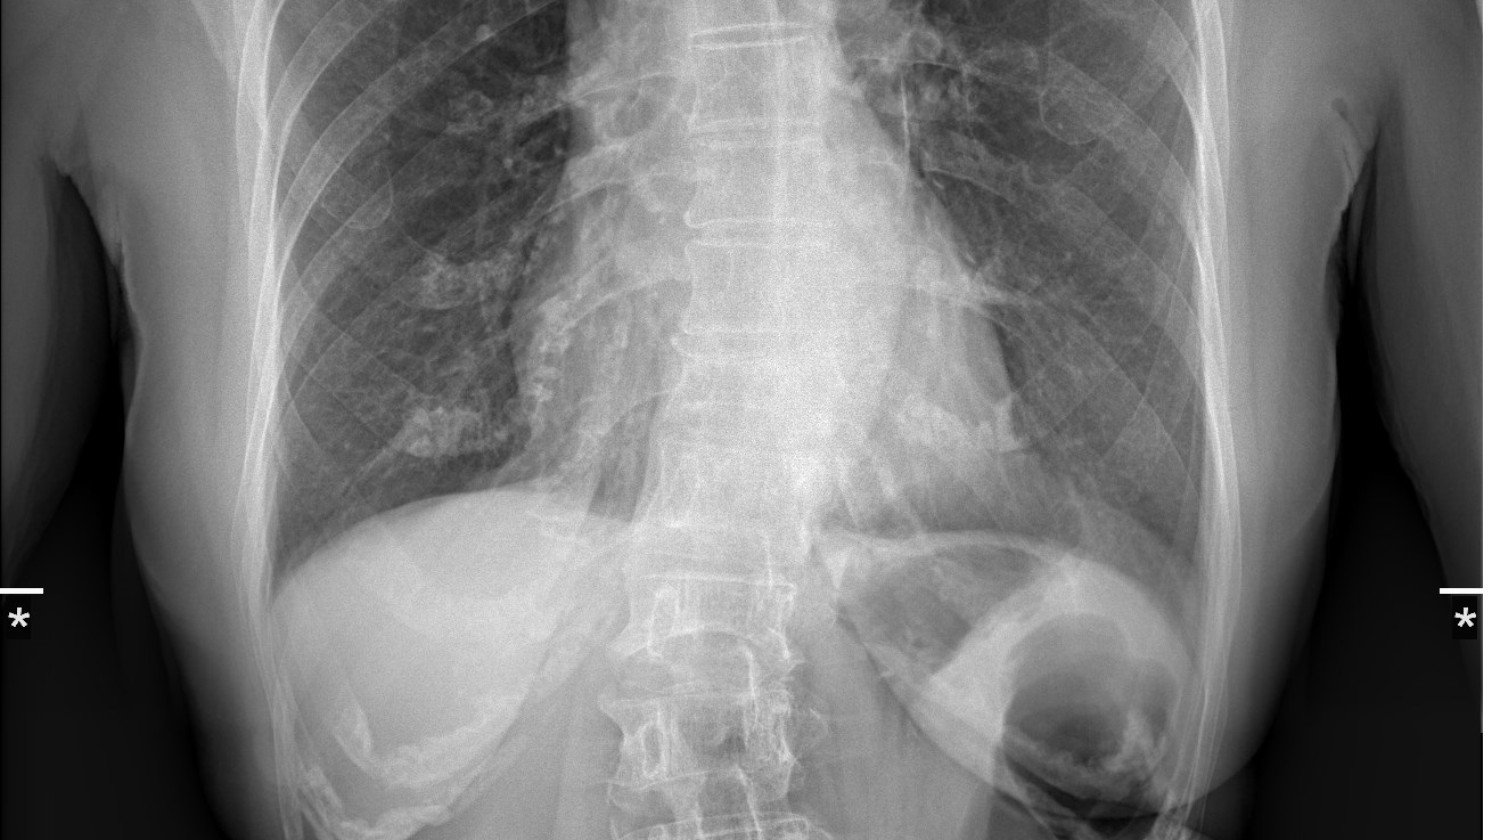

Voit nähdä kuvassa alhaalla muodonmuutoksen ......

Hänellä on useita murtuneita luita ja harvinainen Takayasun oireyhtymä (jota kutsutaan myös Takayasun valtimotulehdukseksi) on harvinainen, krooninen tulehdussairaus, joka vaikuttaa ensisijaisesti suuriin verisuoniin, erityisesti aorttaan ja sen suuriin haaroihin.

🔹 Takayasun arteriitti, harvinainen ja kivulias sairaus, joka tulehduttaa hänen suurimmat valtimonsa ja rajoittaa veren virtausta elintärkeisiin elimiin.

🔹 Osteoporoosi, joka on heikentänyt hänen luitaan niin paljon, että pienetkin liikkeet voivat aiheuttaa kovaa kipua tai murtumia.